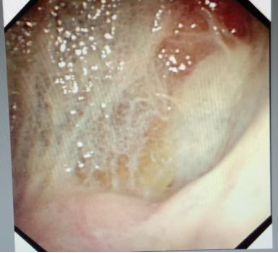

蜘蛛网胸水(包裹性胸腔积液),在胸腔镜下是什么鬼样子的呢?

胸腔里面这么多分隔,你能保证你的针在哪个小分隔里面?除非你有孙悟空的火眼金睛!

在胸腔镜下,是“蜘蛛网+蜂窝状”般的变态存在。

对于包裹性积液,胸腔积液粘稠或分隔形成,B超下的表现,如下图: